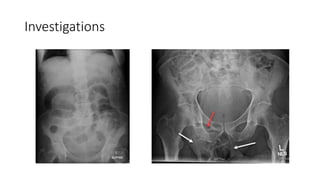

• Abdominal x-ray

• Ultrasonography

Management • Identify complicatedFH • Resuscitate • Empirical antiobiotics • Investigations • Abdominal x-ray • Ultrasonography • In ambiguous cases TRO other differentials • Blood tests • Surgery • NO ROLE OF MANUAL REDUCTION